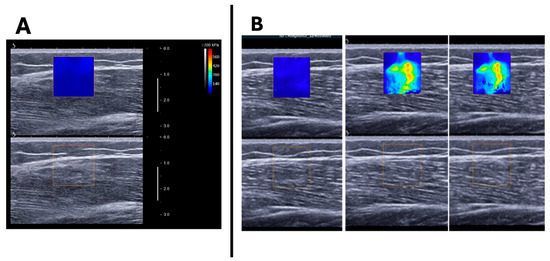

During ramp contractions, the VL shear modulus increased linearly with torque production (Figure 4). The R2, calculated from the individual linear regressions between muscle torque and VL shear modulus (excluding resting values), had a mean value of 0.77 ± 0.33 (range: 0.27–0.99). However, pooling the individual data together, a large variation in the VL shear modulus changes during isometric contraction becomes apparent, particularly at higher contraction intensities (Figure 5B). Polynomial contrasts revealed a significant linear effect between the VL shear modulus and the percentage of isometric MVC [F(1,14) = 37.934; p < 0.001], while the quadratic contrast was not significant [F(1,14) = 0.512; p = 0.482]. This suggests that, at least up to 60% MVC, the VL shear modulus continues to increase linearly without levelling off.

Figure 4.

Typical shear wave elastograms during ramp isometric contractions of increasing intensity. MVC, maximal voluntary contraction. During ramp contraction, as the percentage of maximal voluntary contraction (MVC) increases, the elastogram color shifts from blue to green, indicating an increase in shear modulus and muscle stiffness with higher contraction intensity.